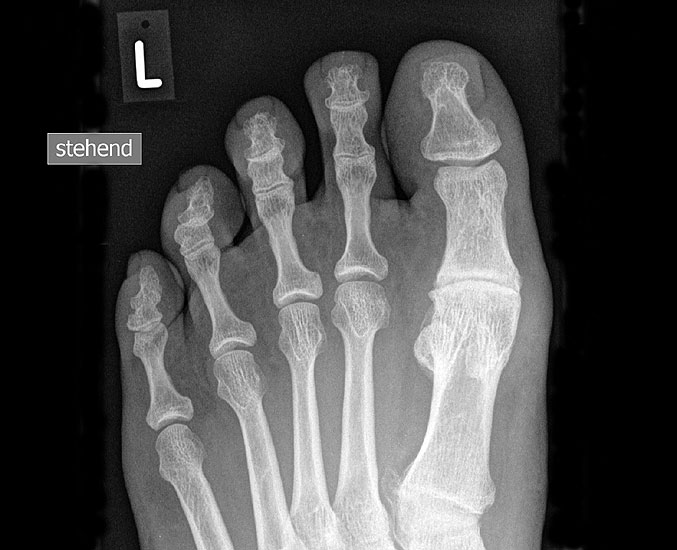

Klinisch zeigt sich stadienabhängig eine schmerzhafte Bewegungseinschränkung mit zunehmender Steifigkeit des Großzehengrundgelenkes. Vor allem die Einschränkung der Dorsalextension wird von den Patienten oft als unangenehm empfunden. Initial besteht eine bindegewebige Alteration im Gelenk, im weiteren Stadium treten Knorpeldegeneration und Begleitsynovialitis mit der Ausbildung von osteophytären Randanbauten auf. Klinische treten diese meist durch eine schmerzhafte dorsale Knochenkante in Erscheinung (Abbildung 1).

Im späten Stadium imponiert eine Gelenkblockierung durch freie Gelenkkörper. Während in den Anfangsstadien vor allem die dorsalen Anteile des Gelenks betroffen sind, betreffen die Veränderungen in den Fortgeschrittenen Stadien die gesamte Zirkumferenz einschließlich des Sesambeingleitlagers. Im Endstadium kommt es zu einer weitgehenden Ankylosierung des 1. Metatarsophalangealgelenks.

• Röntgenaufnahme des Fußes in drei Ebenen unter Belastung